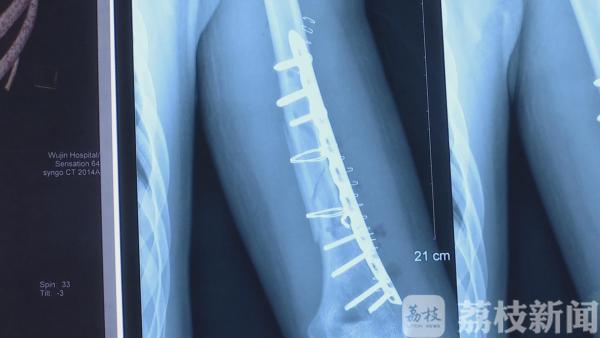

21号上午 , 采访人员从武进人民医院骨科了解到 , 8月7号晚上 , 120救护车送来了一名伤者 , 伤者姓许 , 是一名21岁的大学生 , 左手肱骨粉碎性骨折 。 据伤者说 , 是因为自己和朋友之间掰手腕比力气时受伤的 。

通过X片可以看出 , 伤者骨折极其明显 , 骨头断为两截 。 历医生表示 , 如此严重的骨折一般多出现在外伤事故中 。 此前也遇到过几例掰手腕受伤的 , 但像许同学这种粉碎性骨折 , 他从医近二十年来也是第一次看到 。